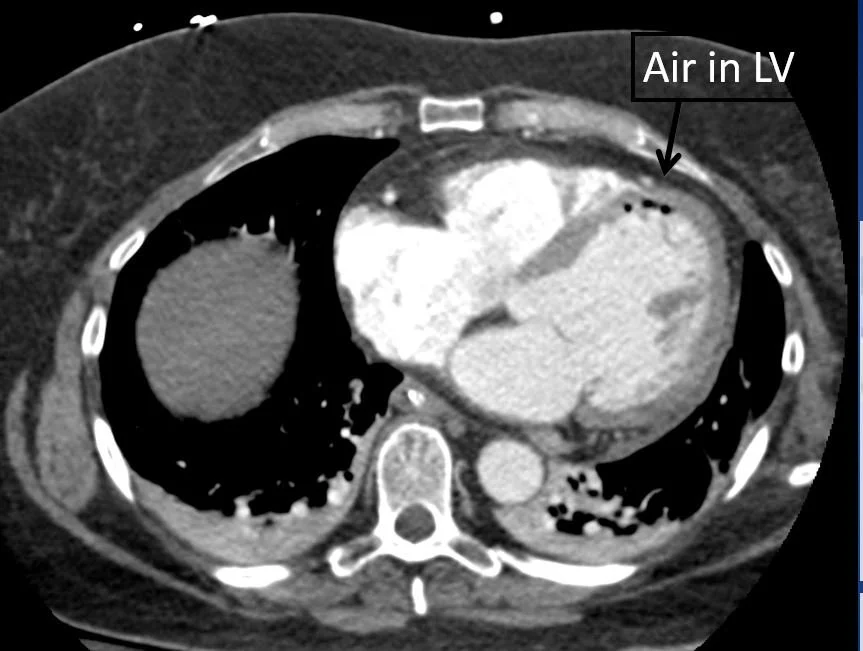

Our patient had an  atrio -esophageal fistula after his ablation and suffered an air embolus causing a stroke.

Air was seen in the LV